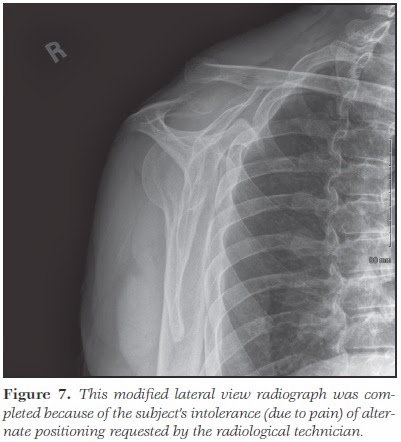

• Não sendo a sua primeira opção, o sujeito consultou o fisioterapeuta, que falou na necessidade de um raio-X para confirmar o diagnóstico de lesão grau III.

• Neste ponto, o médico assistente pediu e analisou estudo radiográfico, que não demonstrou qualquer lesão óssea, concordando com o diagnóstico de lesão Rockwood tipo III.

Embora a deslocação fosse significativa e evidente (Figuras 3 e 5), e já houvesse artrite significativa da articulação, a literatura não suporta a reparação precoce como sendo melhor do que qualquer posterior reconstrução, se a instabilidade se mantiver a longo prazo após tratamento conservador.

Neste paciente, a imobilização precoce para o conforto, atividades funcionais iniciais limitada a menos de 90º, seguidas de padrões funcionais na terceira semana significaram um rápido retorno à amplitude completa de movimento e atividade. O raio-X pode ser suficiente na maioria das lesões para delinear o grau ou tipo de lesão e o tratamento a seguir.